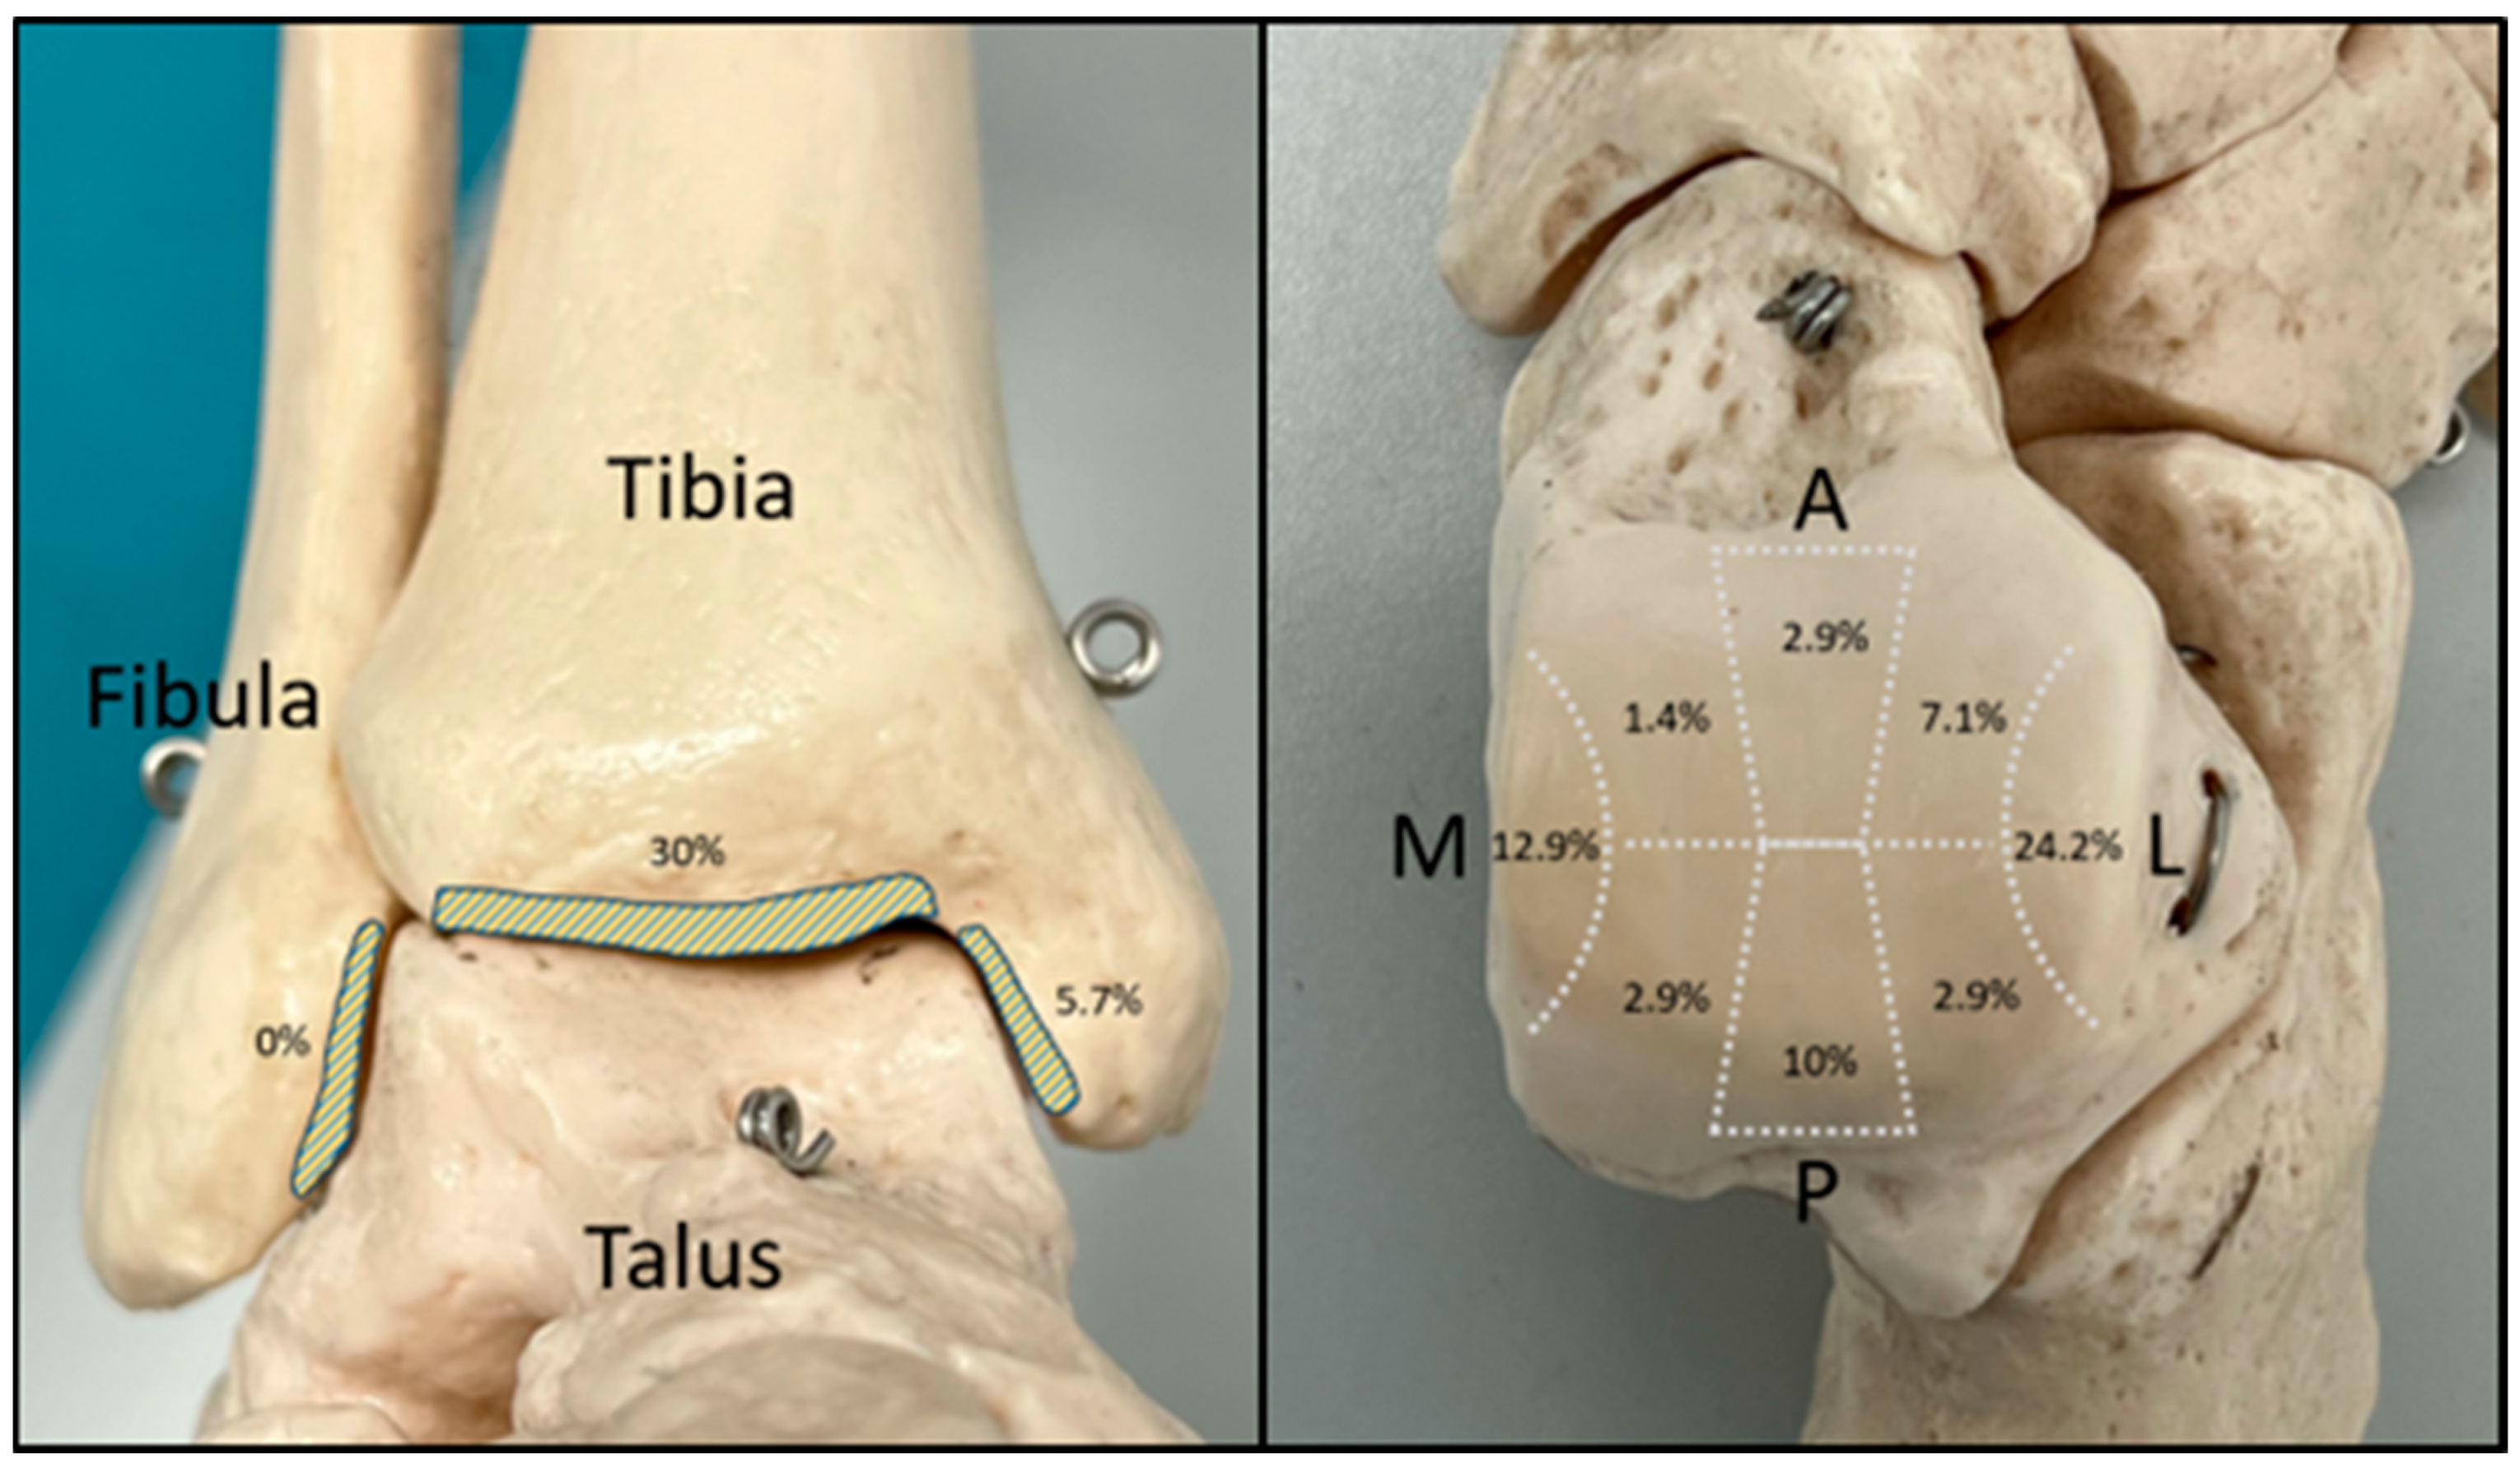

2.4. Assessment of Chondral Lesions

3.2. Evaluation of the Intraoperative Arthroscopic Findings

3.3. Validation